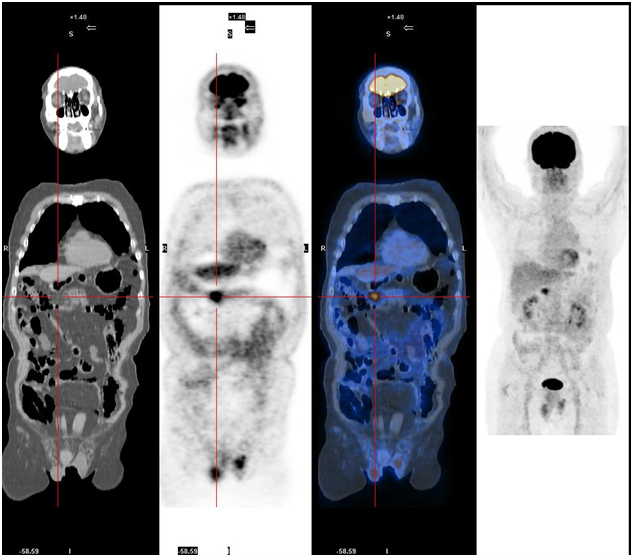

| 女,43歲,PET/CT發(fā)現(xiàn)右肺門區(qū)腫塊影,葡萄糖代謝率明顯增高,手術(shù)病理證實為小細(xì)胞低分化癌。 |